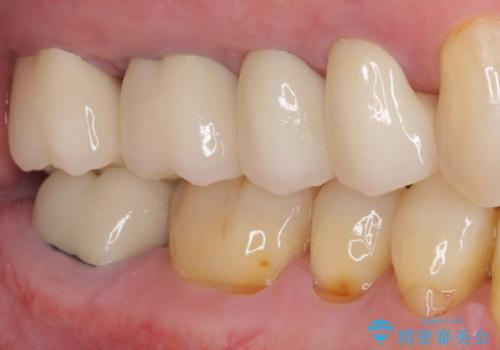

上の歯は見た目を良くしたいというご希望があったため、歯周外科処置を行った歯についてはセラミッククラウンで補綴することとしました。

気になっていた歯の痛みや歯肉からの出血がなくなり、改善したいと思っていた外見も綺麗に仕上がり、大変満足していただきました。